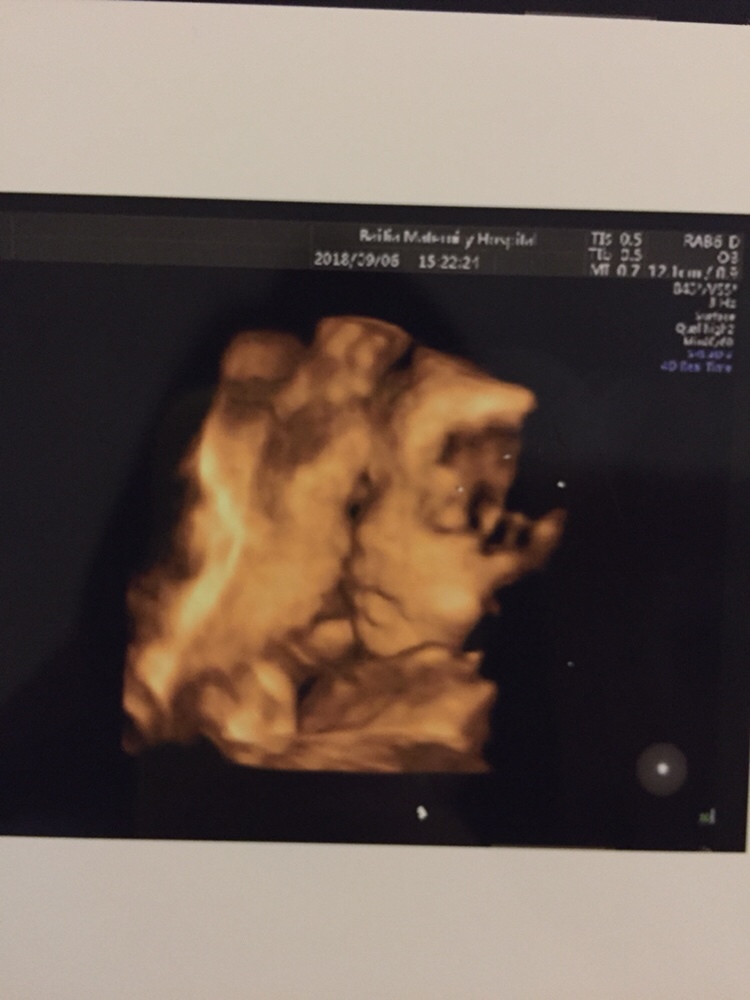

孕22周+3天